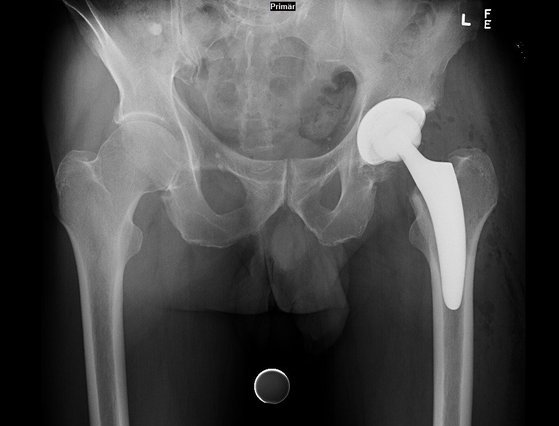

Endroprothetik

Unser Endoprothetikbereich ist voll und ganz auf den Ersatz zerstörter Gelenkflächen oder Gelenke spezialisiert.

Um medizinisch optimal zu versorgen, sind gerade bei der Endoprothetik die neusten OP-Techniken und modernste Standards auf höchstem Niveau erforderlich. Durch die Mitgliedschaft europaweit agierender Gesellschaften ist unsere Endoprothetik hoch spezialisiert und immer auf dem neuesten medizinischen Stand.

Durch die minimalinvasiven muskelschonenden Techniken, ist eine frühzeitige Mobilisierung und Bewegungstherapie möglich. So sind unsere Patienten nach der Operation schneller wieder aktiv, haben deutlich weniger Schmerzen und Bewegungseinschränkungen. Bis zur vollen Belastungsfähigkeit benötigen sie daher nur noch eine kurze Rehabilitationsphase.